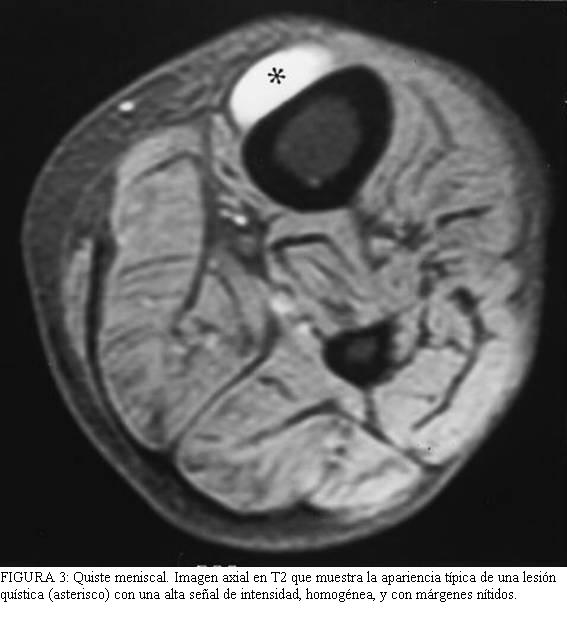

Los

2 y 3) son